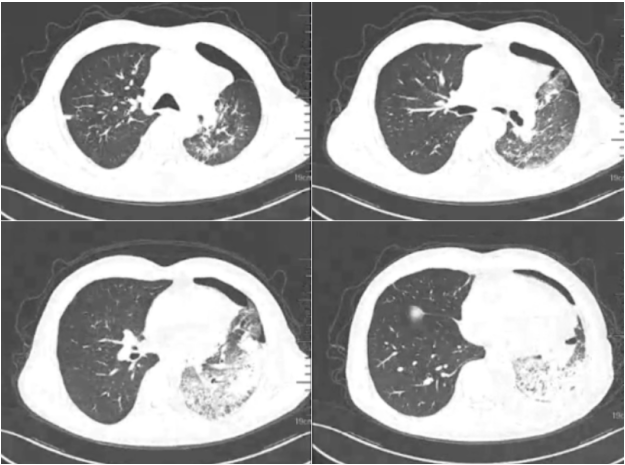

胸部CT(1月27日):左侧液气胸,压缩30%;左肺散在磨玻璃影及实变影;双肺弥漫微小结节,上叶为著;纵膈肺门淋巴结显示并部分钙化(图1)

图1  入院后患者胸部CT表现(1月27日)

辅助检查:胸部CT提示左侧液气胸,左肺散在磨玻璃影及实变影,双肺弥漫微小结节,纵隔肺门淋巴结显示并部分钙化。白细胞及炎症指标升高,诱导痰嗜酸粒细胞比例升高。